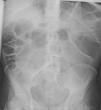

A 38-year-old man with a 20-year history of Crohn's disease presented with weight loss, abdominal distention and vomiting. He had been medicated from diagnosis with 5-aminosalicylic acid and later with azathioprine, which he intentionally stopped 2 years later. His last colonoscopy, dating 5 years before, revealed severe ulceration in the ascending and sigmoid colon. On physical examination the patient was severely emaciated. His abdomen was distended, non-tender, and showed markedly reduced bowel sounds (Fig. 1). His vital signs were normal. Laboratory tests showed mild anemia (12.7g/dL) and C-reactive protein (22mg/L), with normal serum electrolytes. Upright abdominal X-ray showed severely distended bowel loops (Fig. 2), later confirmed by abdominal computed tomography. These findings raised our suspicion for the presence of megacolon. As the patient did not presence signs of systemic toxicity we adopted a conservative approach with intravenous steroids, antibiotics, fluid support, daily abdominal X-ray and evaluation by a dedicated surgeon. On the third day of admission, a colonoscopy was performed showing an ulcerated stricture in the terminal ileum that did not allow passage of the endoscope (Fig. 3). The colon showed no signs of active inflammation. Unexpectedly, MRI-enterography showed severe distention (up to 8cm) of a wide segment of the small bowel proximal to a long stricture. The large bowel appeared not to be significantly distended (Fig. 4). The anatomopathologic examination of the small bowel biopsies showed severe transmural inflammation and architectural distortion compatible with Crohn's Disease. There were also multiple nuclear and cytoplasmic inclusions compatible with cytomegalovirus (CMV) infection. As there was suggestion that the stricture could partially be inflammatory and that the patient might benefit from medical therapy, he was started on ganciclovir and Infliximab. Unfortunately, by the 14th week of therapy there was no significant improvement. Due to progressive weight loss, the patient was scheduled for surgery. Examination of the resection specimen confirmed the long 11cm stricture with severe distention of both the small bowel (11cm) and ascending colon (9.5cm).